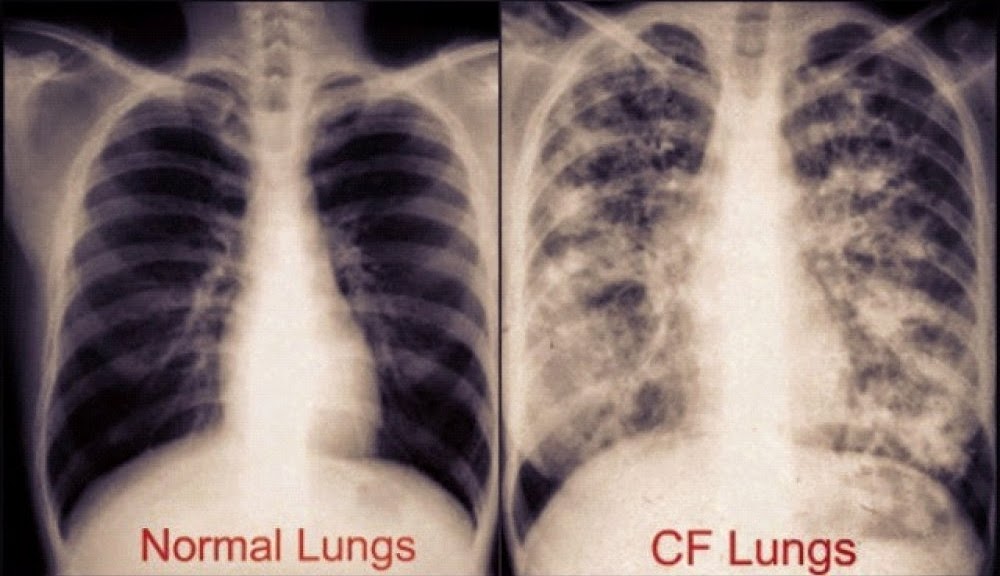

Cystic fibrosis is a genetic disease that affects the lungs and digestive system. People who have cystic fibrosis have thick and sticky mucus in their body which can clog the lungs and obstruct the pancreas.

Cystic Fibrosis symptoms are persistent coughing, shortness of breath, wheezing, poor weight gain,..